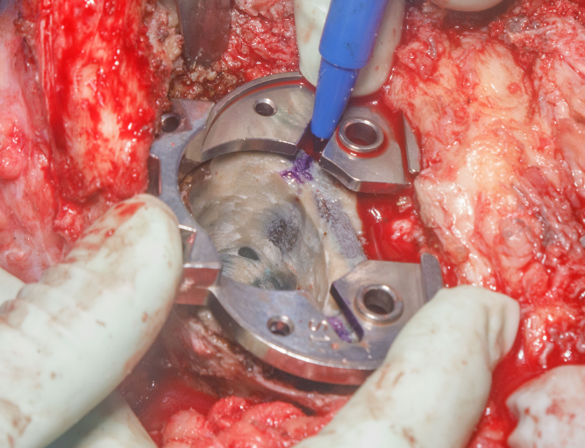

Metallic stained soft tissue on approach. Modular junction failure. Stem and cement mantle removed en bloc. Pt underwent impaction bone grafting of polished/sclerotic canal. Cemented femoral stem with cone. https://t.co/hyA3fGNxF5

Case: 69 yo M w/ hx of left TKA w/ revision x 2 for aseptic loosening. Now with acute worsening left knee pain. Progressive radiolucent lines about femoral stem, change in modular junction appearance. Operative plan? How to address sclerotic canal of multiply revised knee?